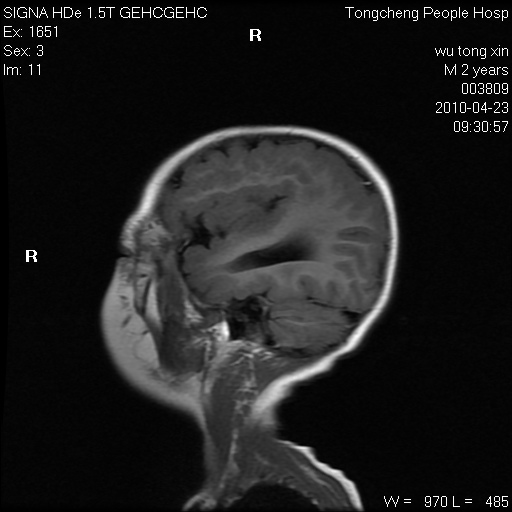

以下是引用赵物学在2010-4-25 12:43:00的发言:[br]巨脑回[br]侧脑室后角低密度影考虑hie或肾上腺脑白质营养不良?[br][br][本贴已被 赵物学 于 2010-4-25 12:51:28 修改过]

以下是引用gaoxiao在2010-4-25 16:54:00的发言:[br]巨脑回畸形。脑白质髓鞘化不良

以下是引用pujunzhi在2010-4-25 21:35:00的发言:[br]考虑 1双侧大脑皮质发育不良 2轻度脑积水 3双侧脑室后角旁片状长t1长t2信号,需继续观察,因为正常小儿此处脑白质的髓鞘化时间可以延迟到4-6岁,才显示正常。